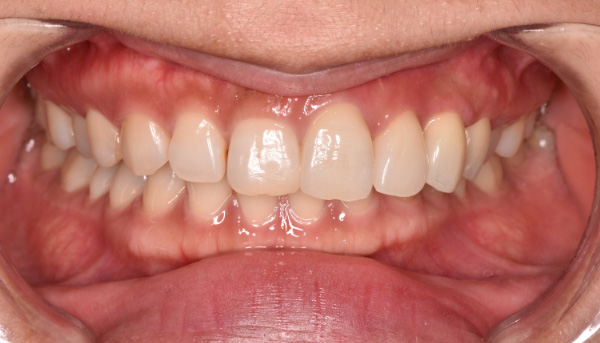

治療後

前歯のインプラントで特に審美的に要求の高い患者様でしたので、当院で最も信頼性の高いインプラント治療プランをご選択いただきました。また、前歯の左右差をコンポジットレジン(CR)修復治療で整えました。

| 主訴 | 根が折れてしまった歯をインプラントにしたい。 合わせて前歯の左右差を治したい。 |

| 治療期間 | 約4ヶ月 |

| 治療費 | 1本あたり550,000円(税別) |

| 治療内容 | 前歯のインプラント治療 |

| 治療のリスク | 前歯のインプラント治療では、審美性の問題や骨密度不足によるインプラントの不安定、神経損傷や感染のリスクがあり、術後の腫れや痛みも発生する可能性があります。 |